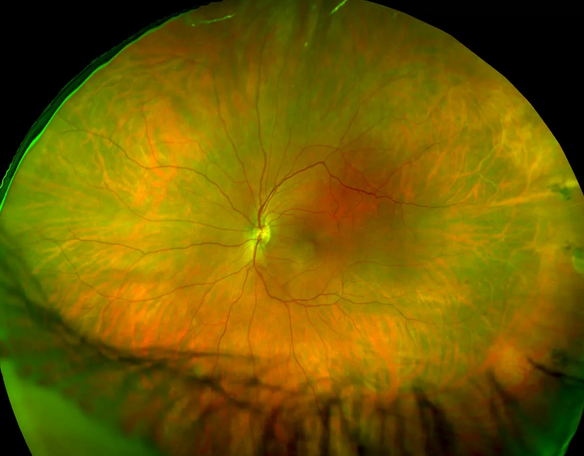

Изображения и анатомия сетчатки глаза